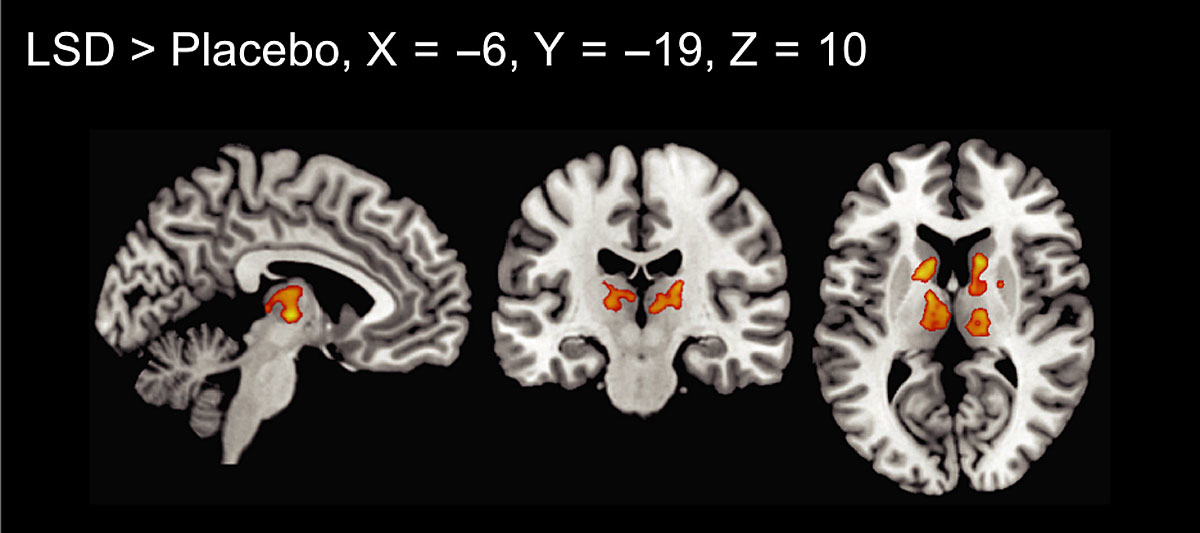

Functional connectivity of the whole brain after LSD administration has been investigated by three studies so far [2, 8, 9, 15]). These studies used a measure called global functional connectivity, which is the mean correlation of a given region to all other regions. An advantage of this measure is that it is data-driven, meaning that no a priori hypotheses, such as which region or network might or might not be affected by LSD, are needed. Tagliazucchi et al. found relatively widespread increases in global connectivity in frontal, parietal, and temporal cortical regions [15]. In more detail, the authors described increased global connectivity in precuneus and thalamus, but no details were reported for other regions [15]. Compared with that, our group found increases in global connectivity that were limited to thalamic regions and part of the basal ganglia ([8, 9] please see fig. 4 for more details). The fact that alterations were spatially less widespread in our sample might be explained by slight methodological differences (global connectivity was calculated based on voxels compared to region of interest) resulting in a stricter statistical threshold.

Figure 4 Global functional connectivity after LSD administration. Increased connectivity was seen in thalamic regions and the basal ganglia (p <0.05, cluster size FDR‐corrected on the basis of a voxel‐threshold of 0.05 FDR‐corrected). Right is right side of the brain. X, Y, and Z values indicate MNI coordinates.

Figure reprinted from Müller F, Lenz C, Dolder P et al. Increased thalamic resting-state connectivity as a core driver of LSD-induced hallucinations. Acta Psychiatr Scand. 2017;136:648-657 [8], with permission from Wiley.